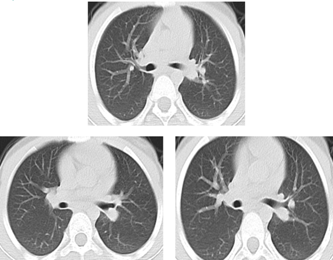

经过规范治疗,小姑娘的症状明显缓解,复查CT(见下图)和气管镜提示左主支气管狭窄明显好转。出院前,小姑娘又重绽笑颜轻松而肆意,那是青春明媚和勇敢的力量,深深地感染了周围所有人,让医护人员的心温暖而满足。